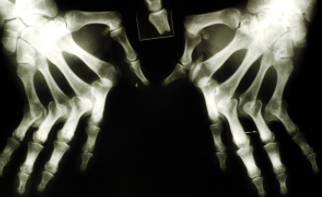

TF16010039 姓名:王先生 性别:男 年龄:41岁

- 病情

痛风 ①晚期 ②并发症 病史:12年+

- 治疗

治疗后手指关节、脚趾关节痛风石完全清除,血尿酸降至正常水平,手脚各关节痛感消失,关节活动恢复到正常状态。 ??